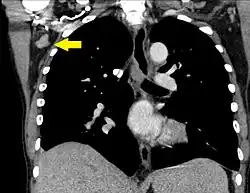

| Mediastinum, generally | 10 mm[31] |

| Superior mediastinum and high paratracheal | 7mm[34] |

| Low paratracheal and subcarinal | 11 mm[34] |